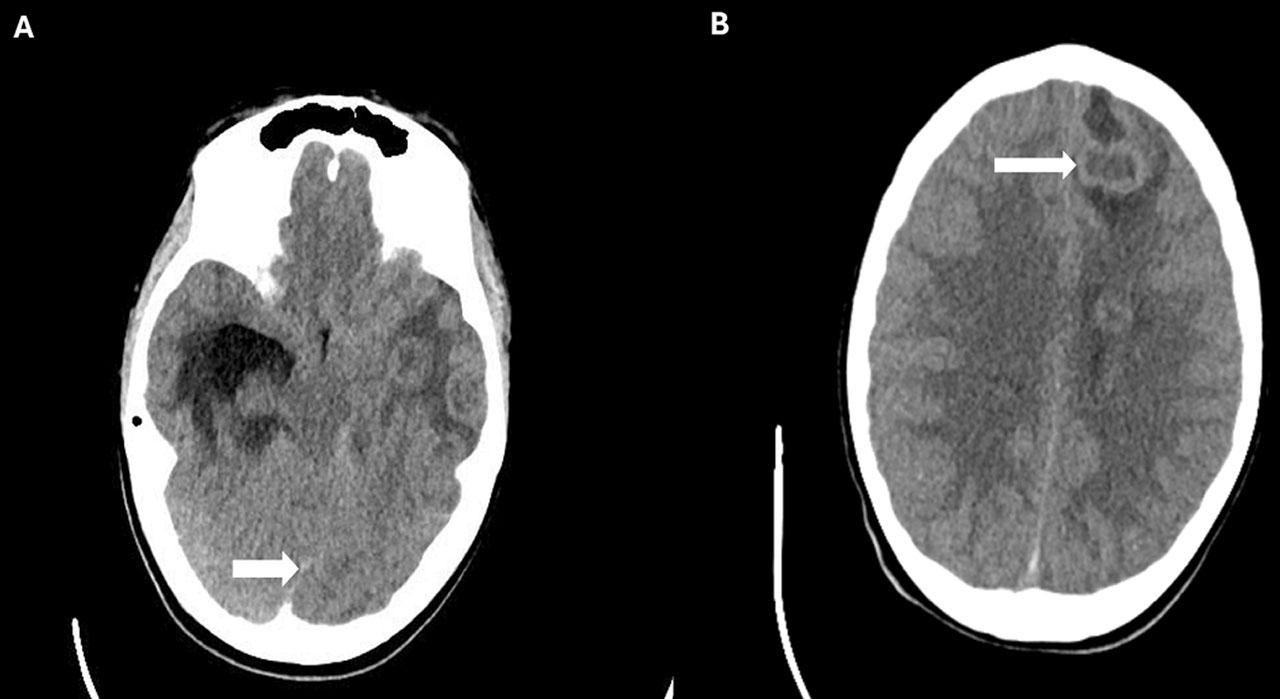

On transfer to our facility for presumptive meningitis, he had fever (Temperature-38.1 Celsius), bradycardia (heart rate between 50–60/minute), and tachypnea (respiratory rate of 28/min). Neurological examination was notable for neck stiffness and a positive Kernig’s sign. IV fluids, vancomycin, ceftriaxone, and acyclovir were started. His condition deteriorated, marked by worsening mental status, severe bradycardia and hypertension. He was admitted to the PICU, intubated, and received dexamethasone and mannitol for raised intracranial pressure (ICP), which did not elicit a response. A head CT revealed multiple supratentorial and infratentorial brain abscesses, midline shift, and hydrocephalus (Figure 1A and 1B).

A: Axial head CT image showing the midline shift (white arrow); B: Axial head CT image showing multiple brain abscesses.